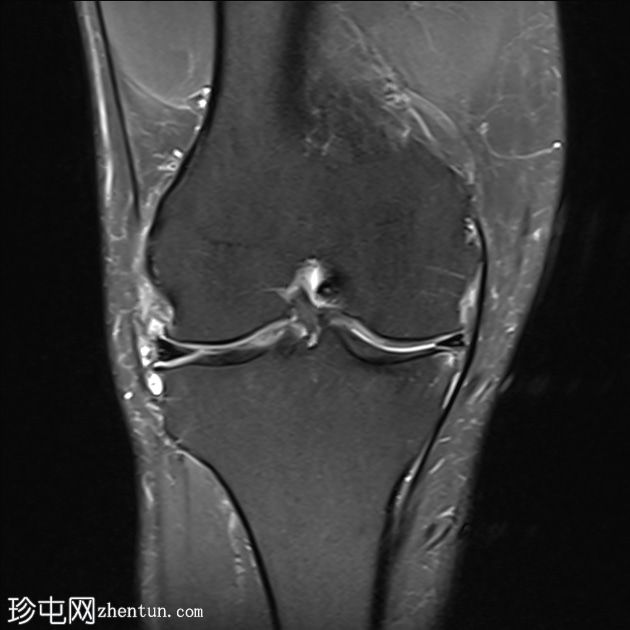

PD脂肪饱和度

T2和PD脂肪饱和序列上可见多处轻微高信号区,位于股四头肌腱远端、前交叉韧带、内侧副韧带近端1/3内表面深层、腘肌腱附着处。

少量膝关节积液。

其他发现包括:前交叉韧带腱鞘囊肿、膝关节后外侧轻度肌间液信号和轻度软骨软化。

印象:这些发现提示痛风性关节炎伴单钠尿酸盐晶体沉积。